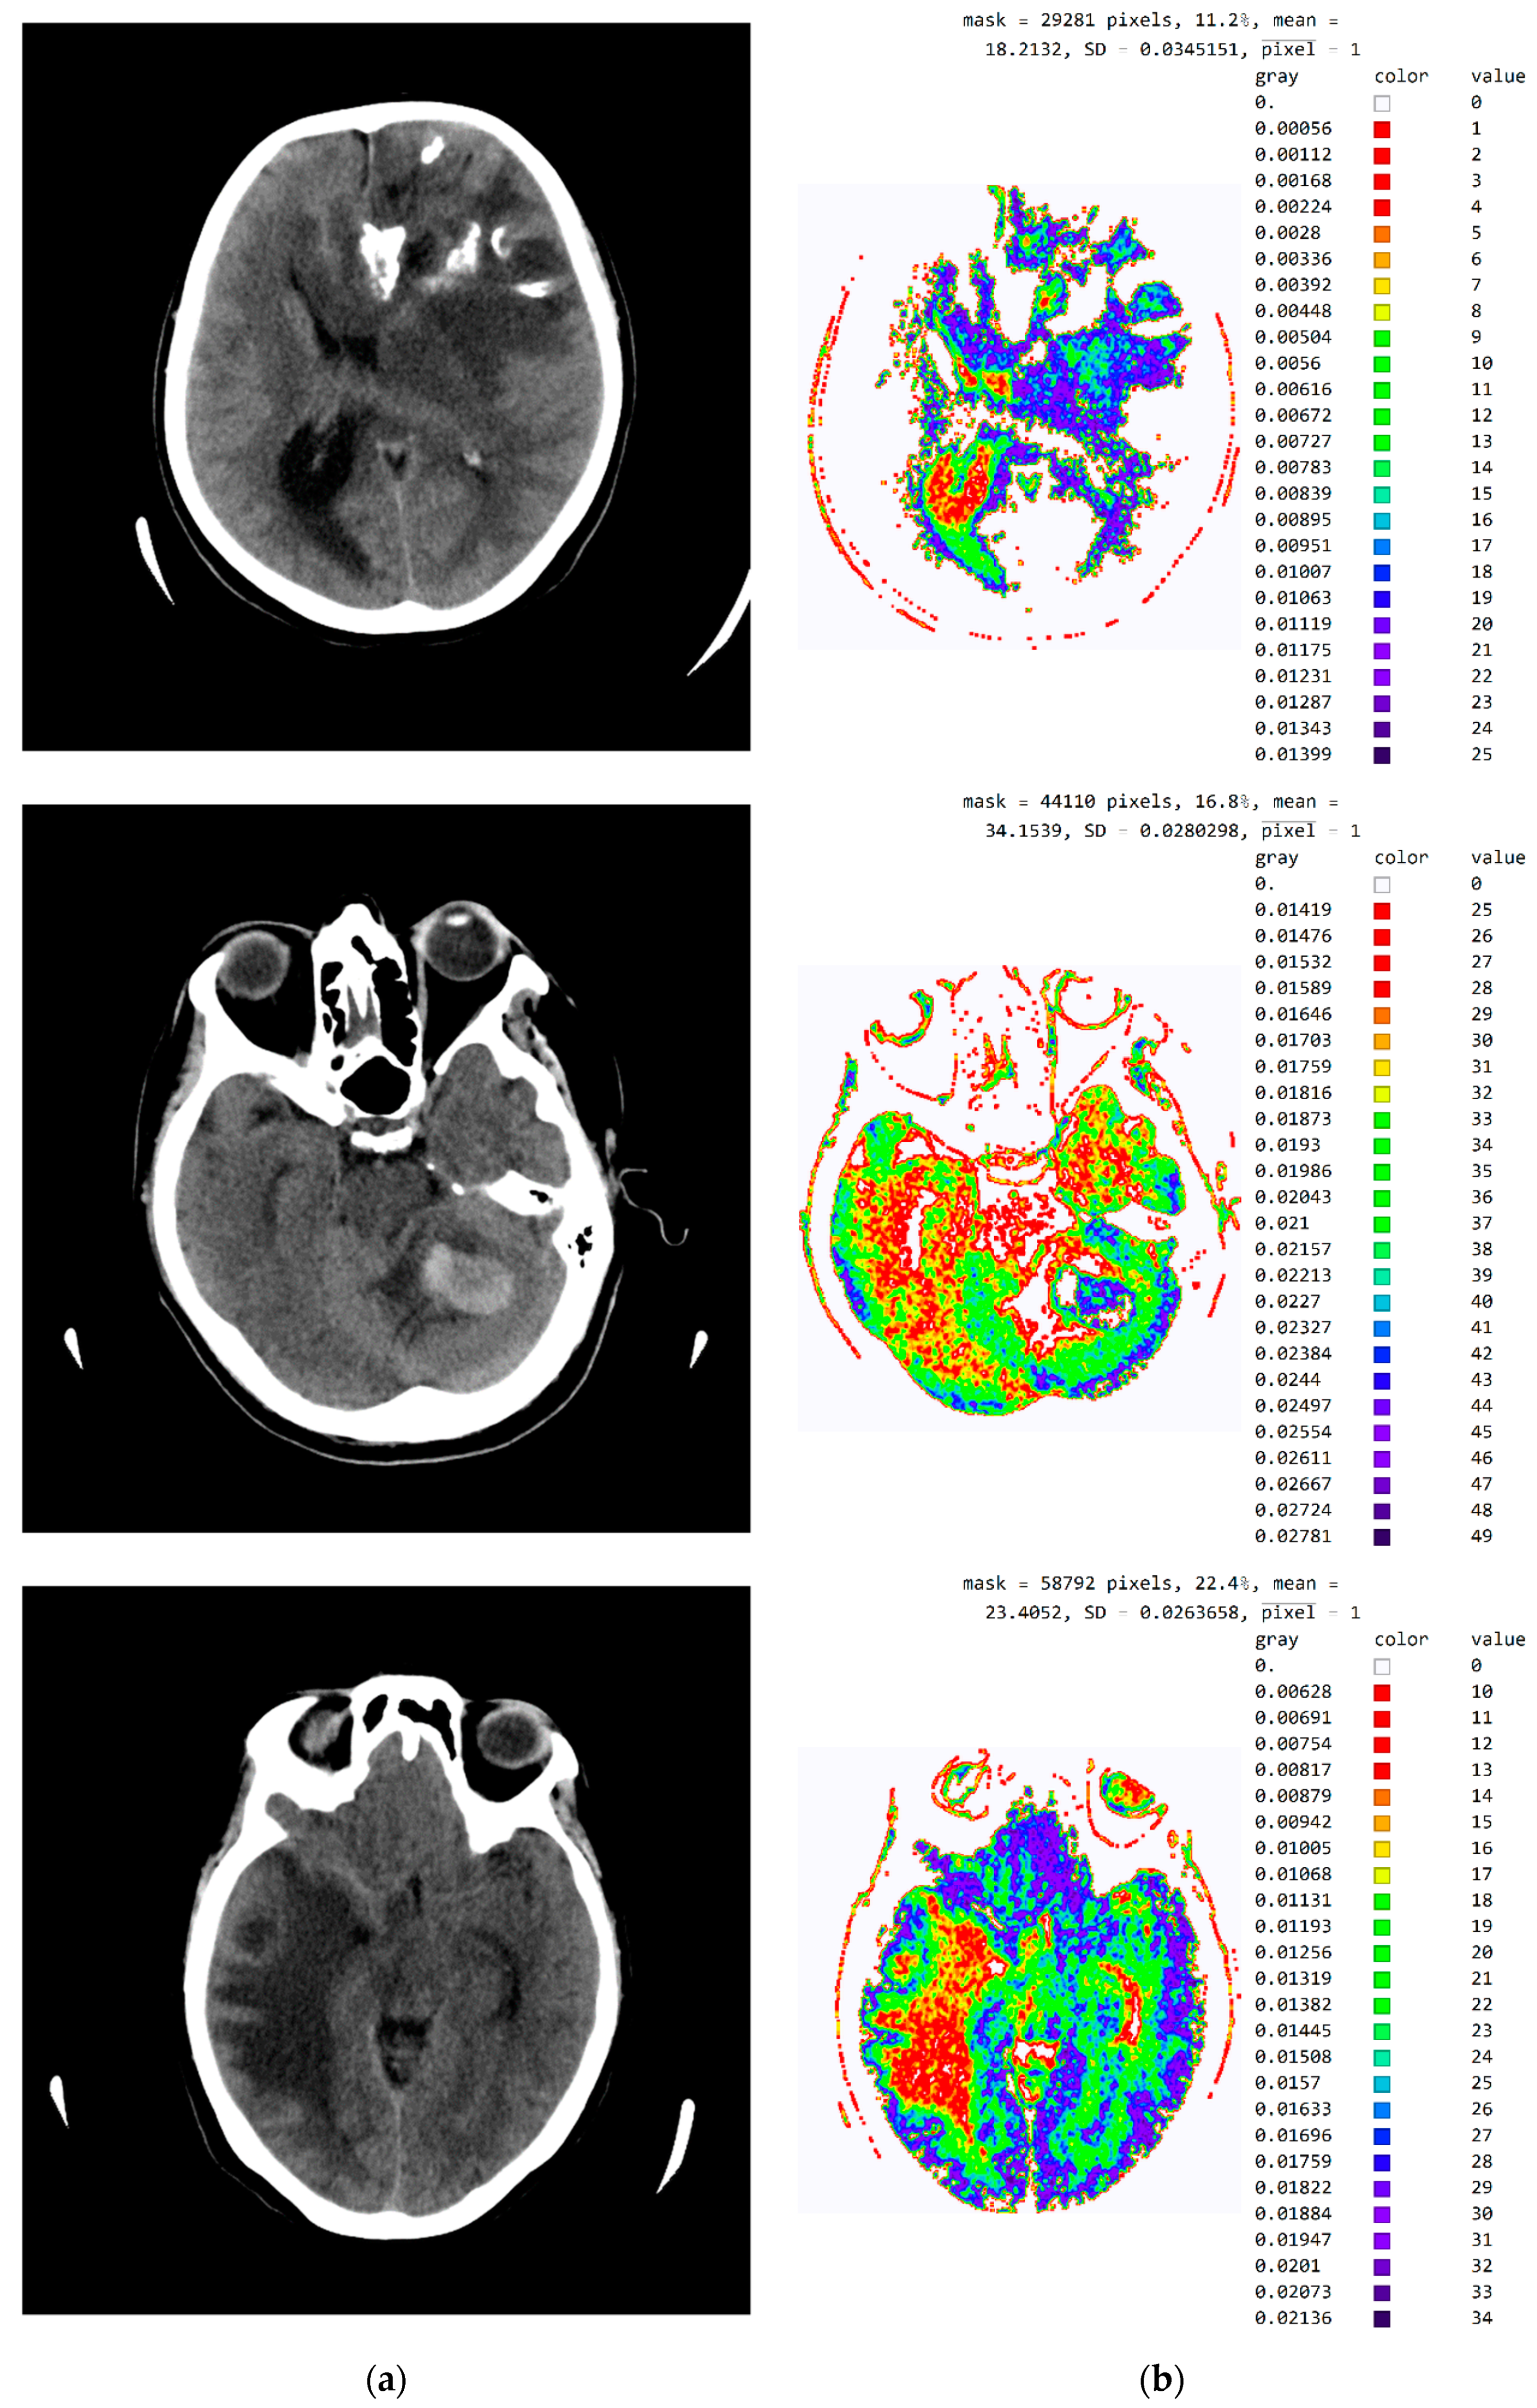

Figure A3 in Appendix A provides a tabular presentation of the various ranges of values and color maps in SVMI processing for different diagnosed brain diseases.

Figure A3.

SVMI processing of non-contrast MDCT image. (a) Non-contrast MDCT image and (b) Smart Visualization of Medical Images SVMI.